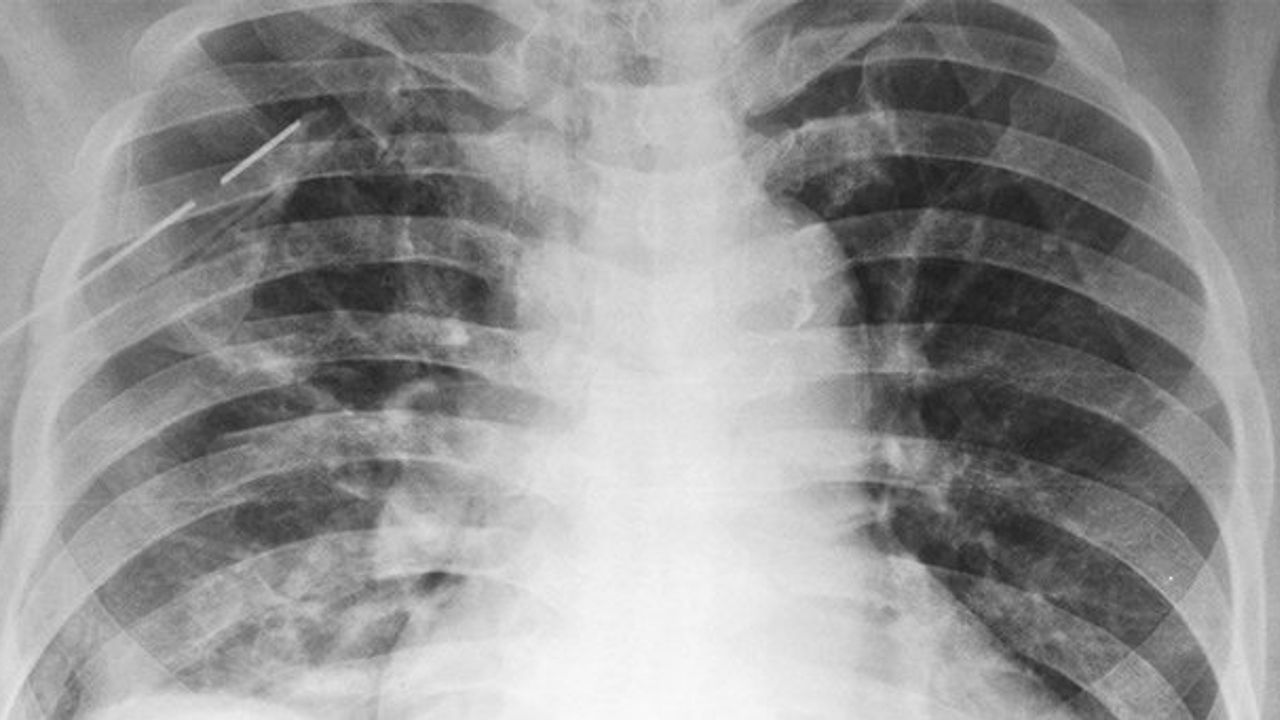

Ani gelen şiddetli göğüs ağrısı ve nefes darlığı ciddi Pnömotoraks'ın en belirgin belirtileridir. Genelde yavaş ve hafif klinik belirti vermesine rağmen ani ve şiddetli gelen göğüs ağrısı-nefes darlığı ile belirti vereren bu hatalıkta ğöğüs ağrısı o kadar şiddetlidir ki, genellikle kalp krizi ile karıştırılır.

Öte yandan pnömotoraks KOAH'lı hastalarda da sık görülen bir rahatsızlıktır. Bu hastalarda öncelikli şikayet nefes darlığıdır. Dolayısı ile KOAH'lı bir hastanın da göğüs ağrısı ve nefes darlığı durumunda KOAH atağı olarak geçiştirilmeden Pnömotoraks ihtimaline karşı da mutlaka tetkik edilmesi gerekir.

Primer spontan pnömotoraks sigara içen, uzun boylu, zayıf ve hafif kambur, genç yetişkin erkeklerde daha sık görülen rahatsızlıktır ayrıca pilot ve dalgıç gibi meslek gruplarını da hedef alıyor. Araştırmalar 100 binde 5-10 kişide görüldüğünü söylüyor. Erkeklerde kadınlardan 6 kat daha sık görülür.

Ülkemizde yılda 13 bin civarında Pnömotoraks vakası saptanmaktadır. Bunların 10 bine yakını yatırılarak tedavi edilmektedir. Hastaların yüzde 40'a yakını 15-45 yaş grubunda ve 3'te biri erkektir. Nadir de olsa büllöz doku kansere dönüşebilme ihtimali var. Akciğerdeki hasarın çok büyük olmasına bağlı hava kaçağının fazla olduğu durumlarda ölümcül sonuçlar doğurabiliyor.

Pnömotoraks tedavilerinde 4 temel ilke vardır. Akciğerin genişlemesinin sağlanması, şikayetlerin ortadan kaldırılması, komplikasyonların önlenmesi ve nükslerin önlenmesi şeklinde. Bunlardan ilki oksijen desteğidir, hava miktarı az olan kişilere uygulanır ve hasta gözlemlenir. Bir diğeri iğne aspirasyonudur.

Tüm bunlara rağmen; genişlemeyen akciğer dokusu varlığında, her iki akciğerde de sönmenin olduğu durumlarda, göğüs kafesi içinde kan birikmesi durumunda, takılmış olan göğüs dreninden devam eden hava kaçağının fazla olması durumunda ayrıca sosyal endikasyonları olan pilot, dalgıç, gemici gibi meslek grupları ile sağlık merkezine uzakta oturan hastalarda cerrahi önerilmektedir. Cerrahide kapalı (videotorakoskopik -robotik) yöntemler kullanılıyor. Bunlar göğüs cerrahlarının en sık yaptığı ameliyatlardandır.

Pnömotoraks alanı yüzde 15'ten büyükse hava kesilene kadar iğne ile boşaltılır. Eğer akciğerden kaçan hava fazla miktarda ise dren takılarak havanın boşaltılması sağlanır. Orta ve büyük derecede Pnömotorakslarda karşı akciğer ve kalbe baskı yapacak durumda olanlarda Tüp Torakostomi denilen yöntem kullanılmaktadır.